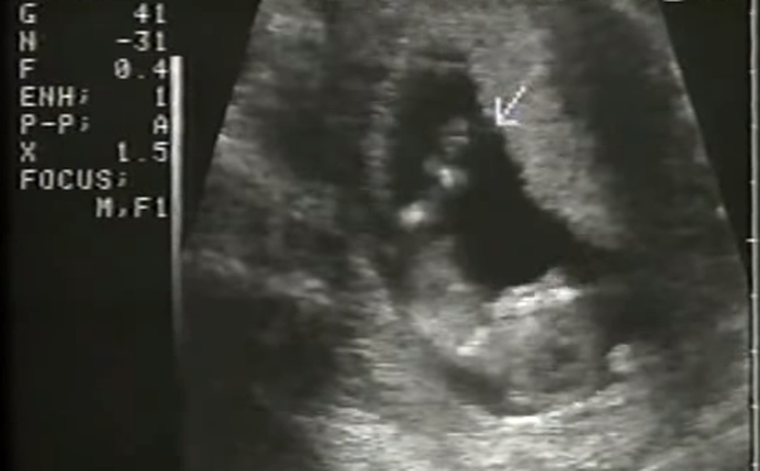

A pocos días del debate en el Senado, un informe muestra lo que la Cámara Alta no trató en comisiones: el costo del aborto.